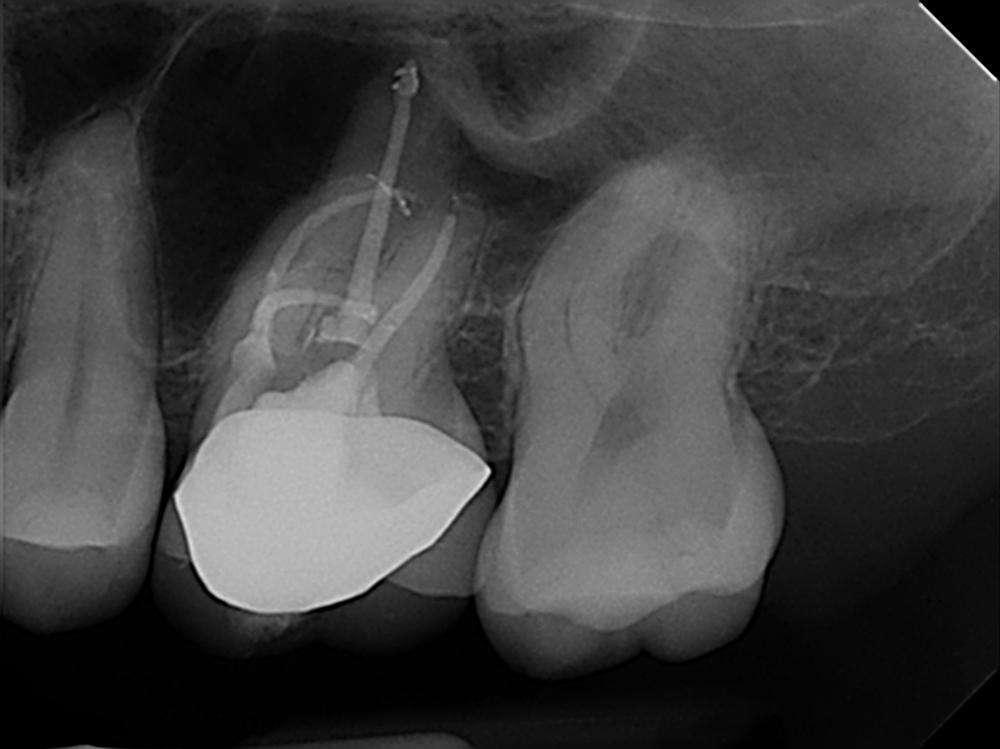

Wenn man sich dieses präoperative Röntgenbild ansieht, sind zwei Hinweise zu diesem endodontischen Fall zu erkennen (Abb. 1): Obliteration der Pulpakammer und enge Kanäle Ungewöhnliche Anatomie der distalen Wurzel

Mit hochtourigen Diamantbohrern wurde eine konventionelle Zugangskavität angelegt und die drei Öffnungen wurden mit Ultraschallspitzen lokalisiert. Die KFeile #08 wurde verwendet, um das endodontische System aller Wurzeln zu erkunden, wobei aber der Apex im distalen Kanal nicht erreicht werden konnte. Das Aufweiten und die Instrumentierung im mittleren Drittel erfolgten mit einer reziprok arbeitenden kleinen (gelben) EdgeOne-Feile (Edge Endo, Albuquerque, NM), die mit Einwärts-Auswärts-Bewegungen von 1-2 mm im Wechsel mit bürstenden Bewegungen zum koronalen Erweitern der Kanäle verwendet wurde. Es wurde eine regelmäßige und reichliche manuelle Spülung mit Lösungen von 5% Natriumhypochlorit durchgeführt. Nach der Aufbereitung des koronalen und mittleren Teils wurde die Arbeitslänge mit der K-Feile #10 bestimmt und das Aufbereitungsverfahren mit martensitischen X7-Instrumenten (Edge Endo, Albuquerque, NM) in den Größen 17 und 25, Konizität .04 abgeschlossen. Die Instrumente wurden mit reziproker Rotation im Uhrzeigersinn (150°-30°) verwendet, um die Torsions- und Biegebelastung zu verringern (Abb. 2).

FALLBERICHT: Abb.1 Abb.2